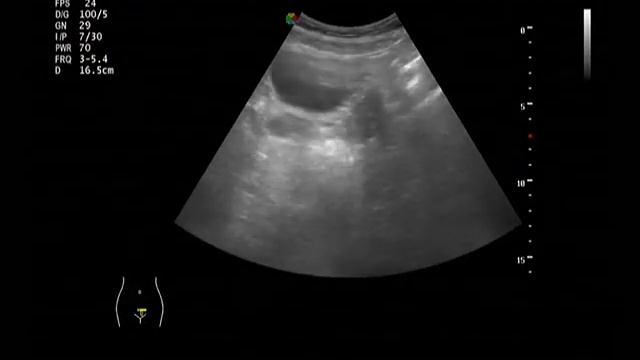

00:00 яичник в паховой грыже 00:12 гидрокольпос 00:31 апоплексия яичника 00:45 беременность раннего срока 00:57 синдром Шерешевского-Тёрнера 01:13 большая кистозная тератома имитирующая мочевой пузырь